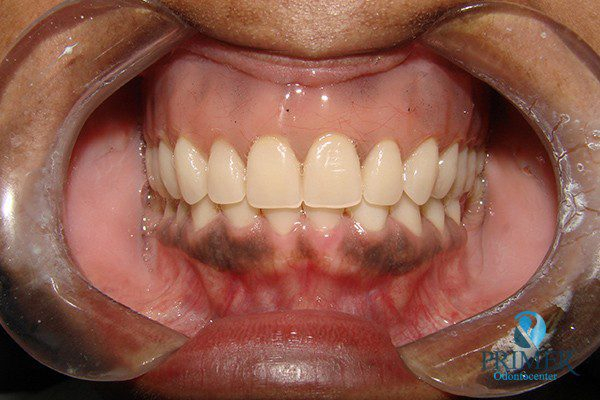

- Antes

- Sorriso inicial